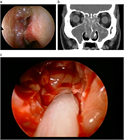

1. 鼻閉感は鼻閉塞に起因することが多いが、上咽頭疾患など鼻腔外の要因でも来し、さらに心身症や萎縮性鼻炎など、閉塞性の病変がなくても生じ得る。

1. 鼻閉を主訴とする疾患で緊急対応が必要なものとして、アスピリン過敏症患者での非ステロイド抗炎症薬(NSAIDs)使用後の急激な鼻閉発作がある。